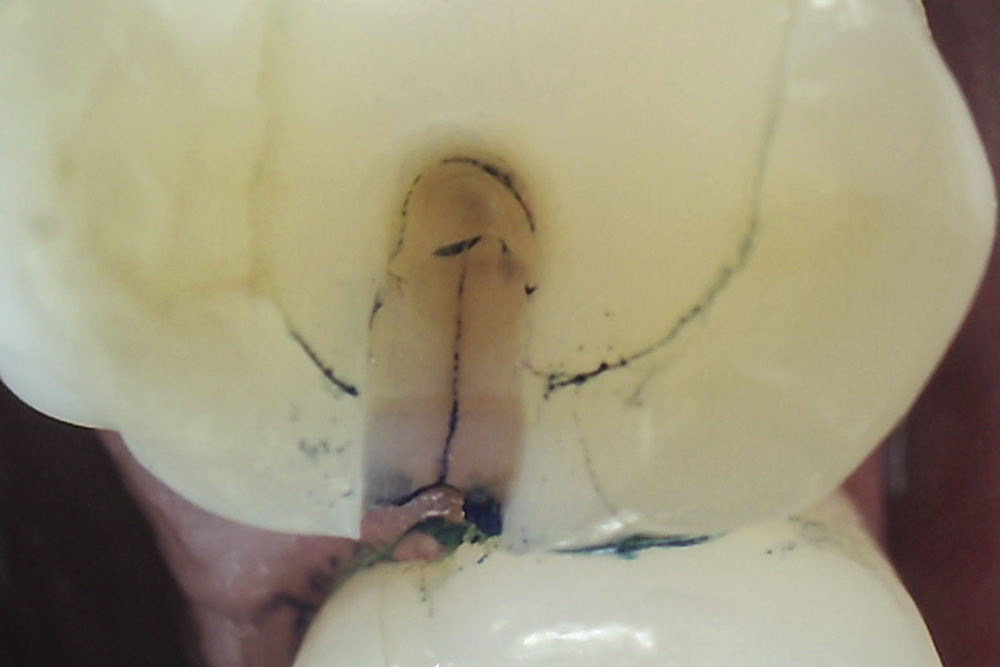

The detrimental effects of vertical cracks on the dentition and surrounding tissues stem mostly from bacterial invasion into the microscopic space of the crack, as well as physical irritation and liquid microleakage, even though the separation of the segments may not be clinically visible.3,5-7 As bacteria penetrate cracks, they invade underlying structures, such as the coronal dentin, pulp, root structure, and periodontal tissues, leading to varying degrees of pathologies. Enamel cracks have been found to provide caries-producing bacteria access to the dentin-enamel junction, leading to caries inside the tooth without any externally visible evidence (Figure 1).5 Dentin cracks are pathways of bacteria to the dentinal tubules and pulp, leading to various pulpal pathologies, including reversible and irreversible pulpitis and pulp necrosis.6,8

Fig 1. Decalcification in enamel along a crack line (arrow) and caries at the dentin-enamel junction of a mandibular left first molar (disto-occlusal view).

Figure 1